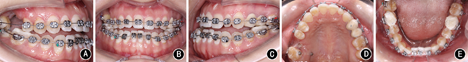

矫治后患者面型好,正面观患者面部对称,侧面直面型。上下颌牙列排列整齐,上前牙未发生明显唇向倾斜,下前牙去代偿。磨牙中性关系,前牙覆

覆盖正常。

过小牙修复间隙预备,维持

修复间隙。全口曲面体层X线片示牙根排列基本平行。患者对治疗早期即解决主诉感到满意,术后正畸阶段患者因妊娠而放弃前牙精细调整。

像;B:正面

像;C:左侧

像;D:上颌

面像;E:下颌

面像